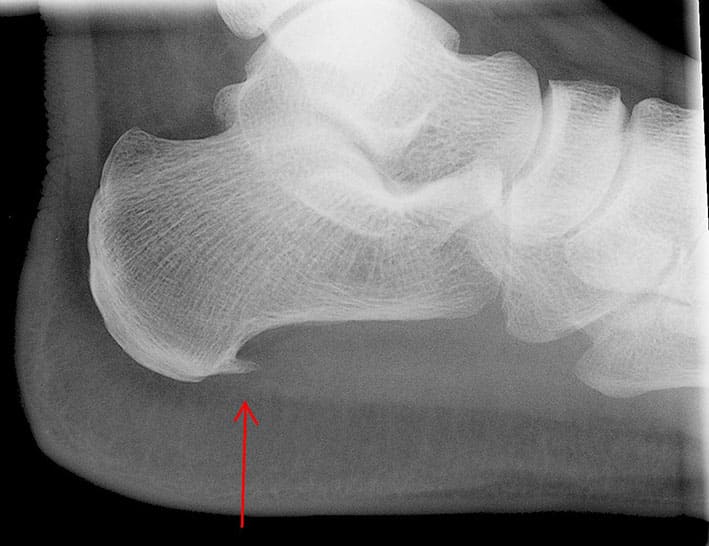

Пяточная шпора – это кальцинированный нарост на пяточной кости, так называемый остеофит. Он может образоваться в результате травмы, ревматизма, плоскостопия, а также больших физических нагрузок, в результате чего нагрузка большей частью оказывается в области стопы. В эти моменты, сухожилия пятки надрываются и травмируются, при этом воспаленные сухожилия, постепенно замещаются рубцом. Этот рубец является благоприятным местом для отложения кальциевых отложений, которые со временем образуют костный кальцинированный выступ – пяточную шпору, который можно легко увидеть на рентгеновском снимке.

Пяточная шпора – это кальцинированный нарост на пяточной кости, так называемый остеофит. Он может образоваться в результате травмы, ревматизма, плоскостопия, а также больших физических нагрузок, в результате чего нагрузка большей частью оказывается в области стопы. В эти моменты, сухожилия пятки надрываются и травмируются, при этом воспаленные сухожилия, постепенно замещаются рубцом. Этот рубец является благоприятным местом для отложения кальциевых отложений, которые со временем образуют костный кальцинированный выступ пяточную шпору, который можно легко увидеть на рентгеновском снимке.